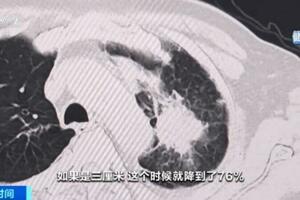

在醫院之後,我給患者進行了MoCA量表和MMSE檢測,結果提示患者已經處於中重度痴呆狀態,屬於典型的阿爾茲海默病。

阿爾茨海默病是老年人的腦部疾病,患者的腦細胞會急速退化,但並不是正常的衰老過程。

阿爾茲海默病占老年痴呆的一半以上,多發生於大於65歲以上的人群,痴呆的發生呈進行性加重的過程,剛開始起病不易察覺,發展緩慢,最早期往往是以逐漸加重的健忘開始,甚至有些老年人表現為脾氣性格的改變出現心煩易怒,變得「內向」、多疑,不喜與人交流,喜歡自己一個人獨處。